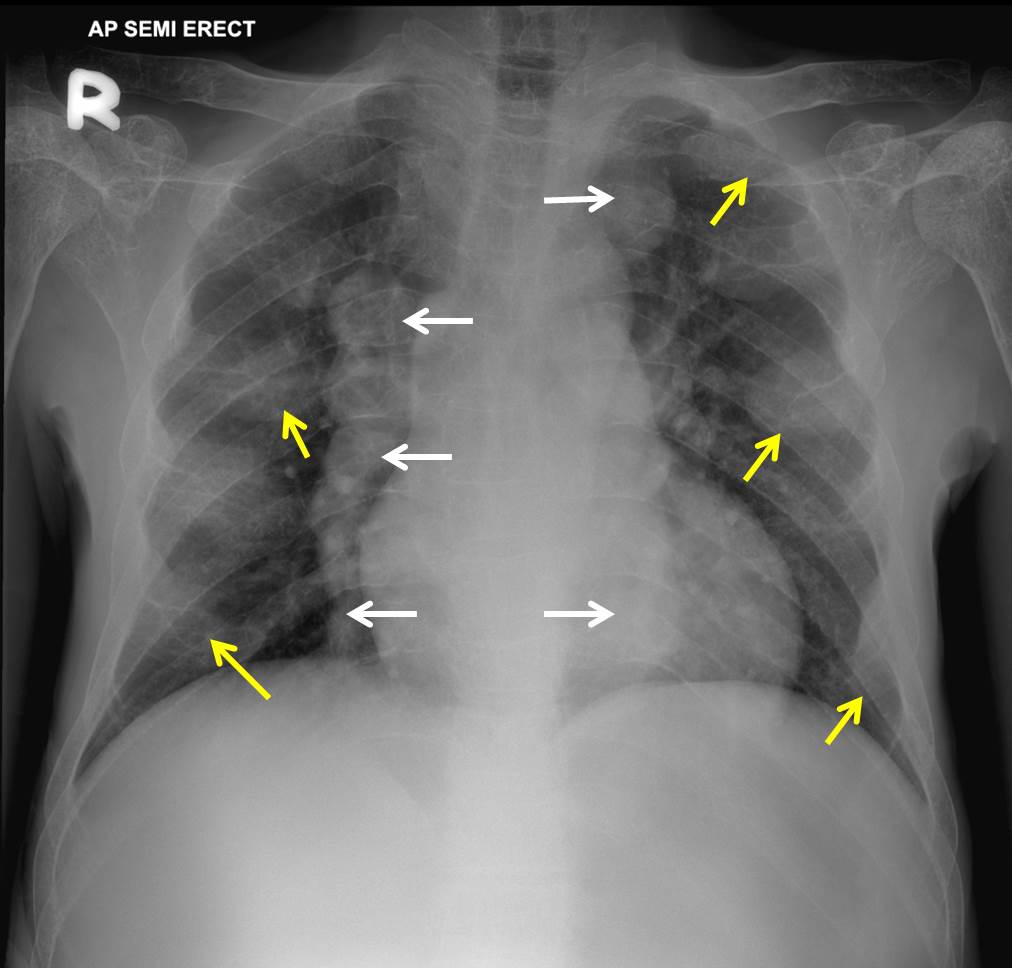

Upper lobe diversion Radiology Cases Chest Radiology Cases Normal ct chest for reference. top 100 ct scan quiz. the education committee of the str is pleased to present the case of the month in thoracic and cardiac imaging. browse chest radiology cme and learn from the top chest radiologists in the world. learn & practice radiology. View all chest radiology courses, watch bite. By. Chest Radiology Cases.